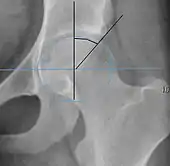

| Measurement | Image | Target | Normal value |

|---|---|---|---|

| Center-edge angle of Wiberg | ![]() |

The superior-lateral coverage of the femoral head. | |